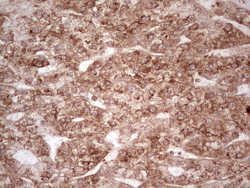

- Main image

- Experimental details

- Immunohistochemical staining of paraffin-embedded Human lymphoma tissue using anti-WIBG mouse monoclonal antibody. (Heat-induced epitope retrieval by 1 mM EDTA in 10mM Tris, pH8.5, 120C for 3min, TA806496)

- Validation comment

- IHC